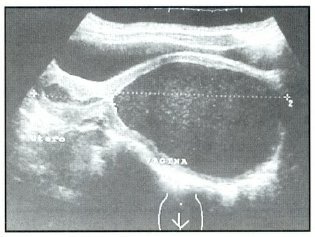

Fig: 3 Hematometra y Hematocolpos

La paciente es operada con el diagnóstico de tabique vaginal transverso incompleto a pesar de no demostrarse solución de continuidad en la vagina. Los reportes ecográficos y TAC reportaron hematometra gigante con hematocolpos y presencia de posible tabique vaginal en 1/3 inferior de vagina, que coincide con el examen físico que mostraba un tabique vaginal completo (Fig: 1,2,3,4).